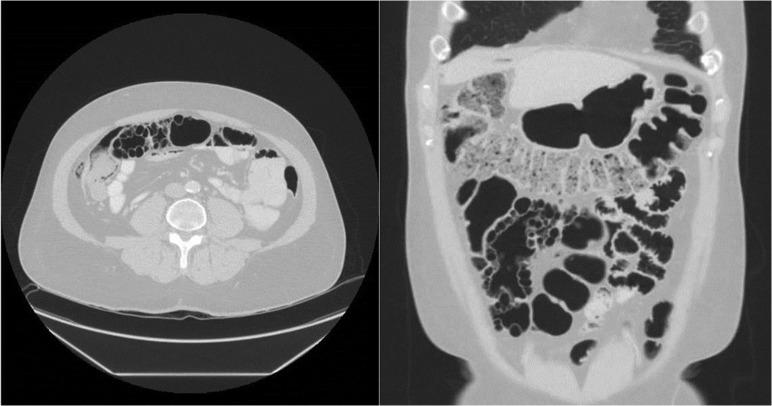

This is a case of a 54-year-old gentleman who presented to an outside hospital emergency department with lower abdominal pain. Computed tomography imaging showed a small amount of intraperitoneal free air and cystic pneumatosis coli. He was admitted, managed conservatively with intravenous antibiotics, and then discharged home after his symptoms improved. Elective laparoscopic sigmoid colectomy was subsequently performed with intraoperative findings of partial sigmoid volvulus and extensive pneumatosis coli of the sigmoid colon. Pneumoperitoneum was determined to be from ruptured intramural cysts. The etiology of pneumatosis coli was likely from chronic sigmoid volvulus.

这是一名54岁男性患者的病例,他因下腹部疼痛前往外院急诊科就诊。计算机断层扫描成像显示腹腔内有少量游离气体和结肠囊样积气。他入院后接受了静脉抗生素保守治疗,症状改善后出院。随后进行了择期腹腔镜乙状结肠切除术,术中发现部分乙状结肠扭转和乙状结肠广泛积气。确定气腹是由壁内囊肿破裂所致。结肠积气的病因可能是慢性乙状结肠扭转。